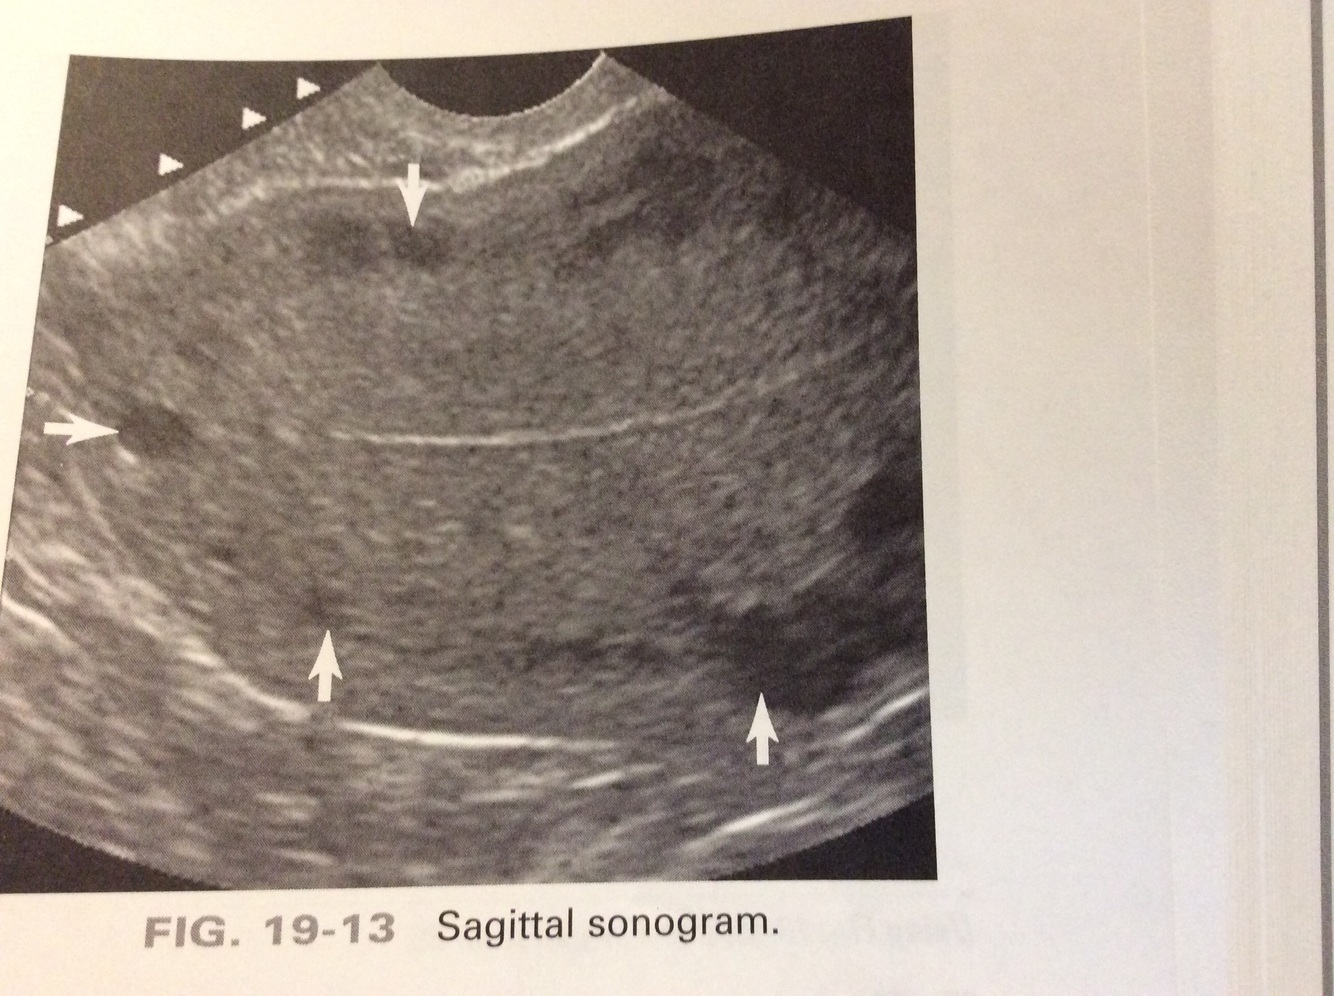

Which pelvic muscles are the arrows identifying?

a) iliopsoas

b) levator ani

c) uterosacral

d) obturator internus

b: The levator ani and pisiform is muscles form the pelvic floor and lie posterior to the vagina. Obturator internus and iliopsoas muscles are located in the lateral true pelvis.

A 30yr old patient presents with a history of dysmenorrhea. The arrows in the sonogram are most likely identifying:

a) leiomyomas

b) adenomyosis

c) arcuate vessels

d) uterine arteries

c: Evenly spaced, hypoechoic or anechoic, circular structures identified in the outer portion of the myometrium most likely represent arcuate veins. Uterine arteries are located in the broad ligament lateral to the uterus.